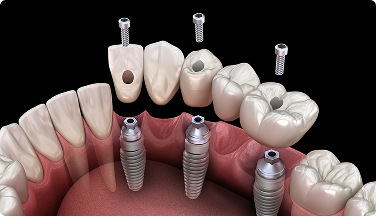

• 발치와 임플란트 뿌리(픽스처) 심는 수술을 동시에 진행하는 방식입니다.

• 골유착이 완료될 때까지 임플란트 상부(치아 머리)는 없이 기다립니다.

임플란트 식립 즉시 수복

• 임플란트 뿌리를 심은 직후, 예비 치아를 즉시 장착하는 방법입니다.

• 24시간 이내에 치아의 외형을 회복하는, 진정한 의미의 원데이 임플란트라고 할 수 있습니다.